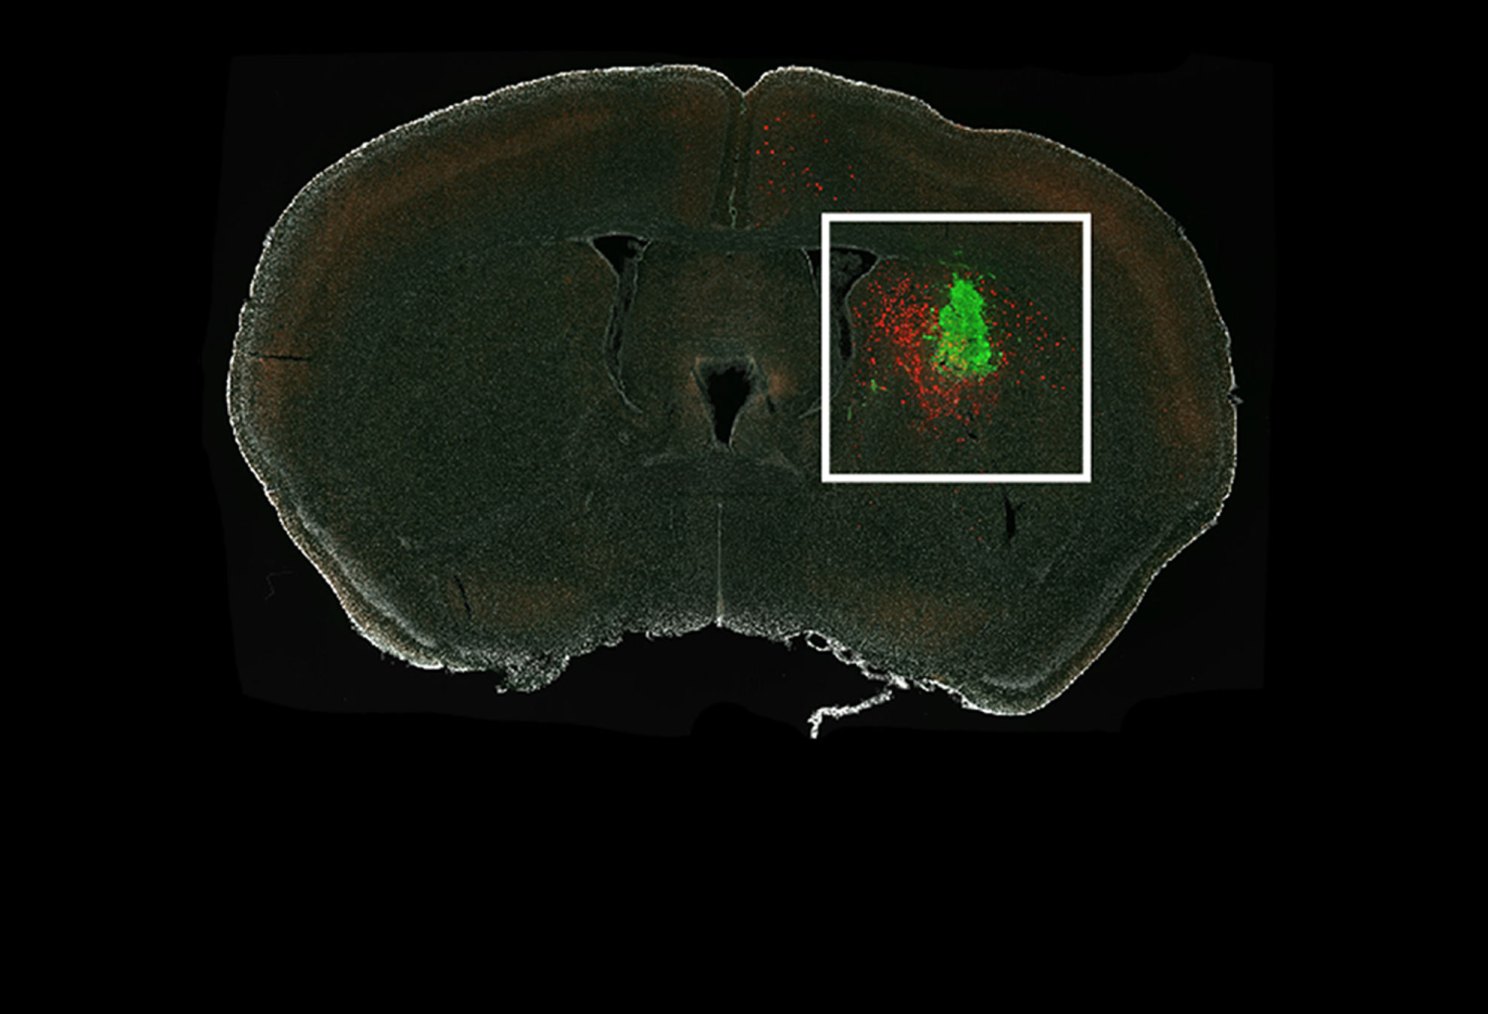

Researchers revealed which neurons in a mouse brain, shown in red, connect to a human glioma, shown in green.

Hsieh and team successfully traced the glioma-innervating neurons back to their sources using a rabies virus engineered to infect only specific cells of interest and to light up those cells when it gets in. The virus travels from the tumor cell back through the neuron that connects to it.

The researchers injected human glioma cells into the brains of mice and waited for neurons to connect with the tumors. They then applied the rabies virus to light up cells of interest. Soon, they had a picture illuminating the mouse brains showing all the glowing neurons that led to the glioma.

The maps revealed that the gliomas hook into existing patterns of neuronal wiring.

And those neurons originate from across the brain, the researchers observed.